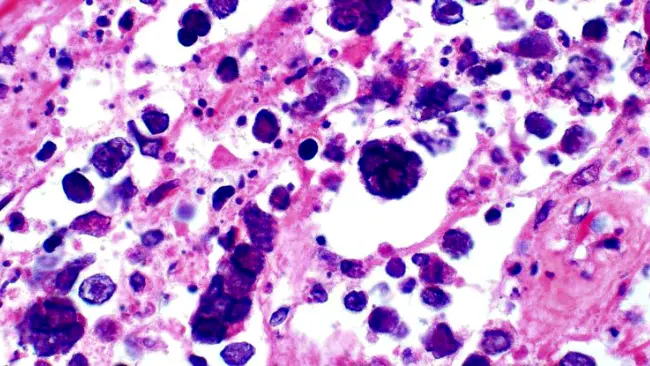

Kanker Kulit

Kalau kulit kering, menebal, bersisik merah, dan berdarah kalau tergores, ini merupakan tanda penyakit serius lainnya, yaitu kanker kulit. Tapi, ada banyak tanda lain pada kanker kulit, girls. Seperti hilang timbul dan bisa saja nggak sembuh-sembuh. Sebaiknya, kalau ada keluhan soal kulit kering yang nggak biasa, sebaiknya konsultasikan ke dokter, ya!